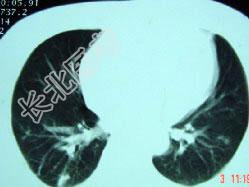

- 单项选择题男,32岁, 外出旅游1个月后,咳嗽1周, CT检查如图,最可能的诊断为 ( )